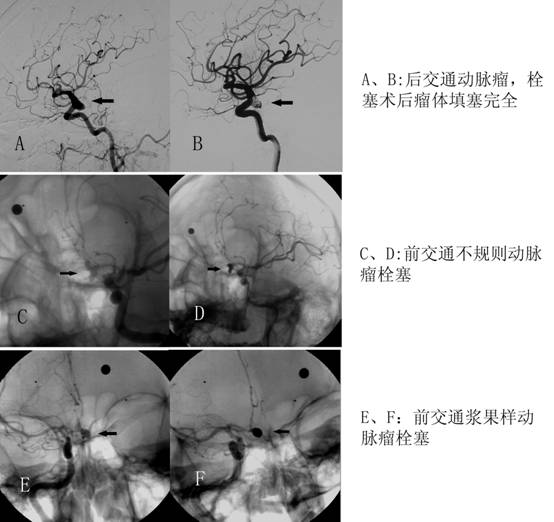

• 神经介入治疗介绍

神经介入治疗介绍

神经介入是指利用血管内导管操作技术,在计算机控制的DSA系统的支持下,对累及人体神经系统血管的病变进行诊断和治疗,达到栓塞、溶解、扩张、...

发布时间:2015-12-25 来源: